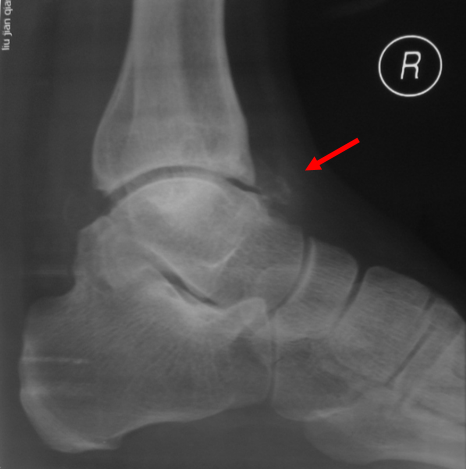

踝关节撞击征

刘建强 男  30岁

外踝骨折

王岩  男  24岁